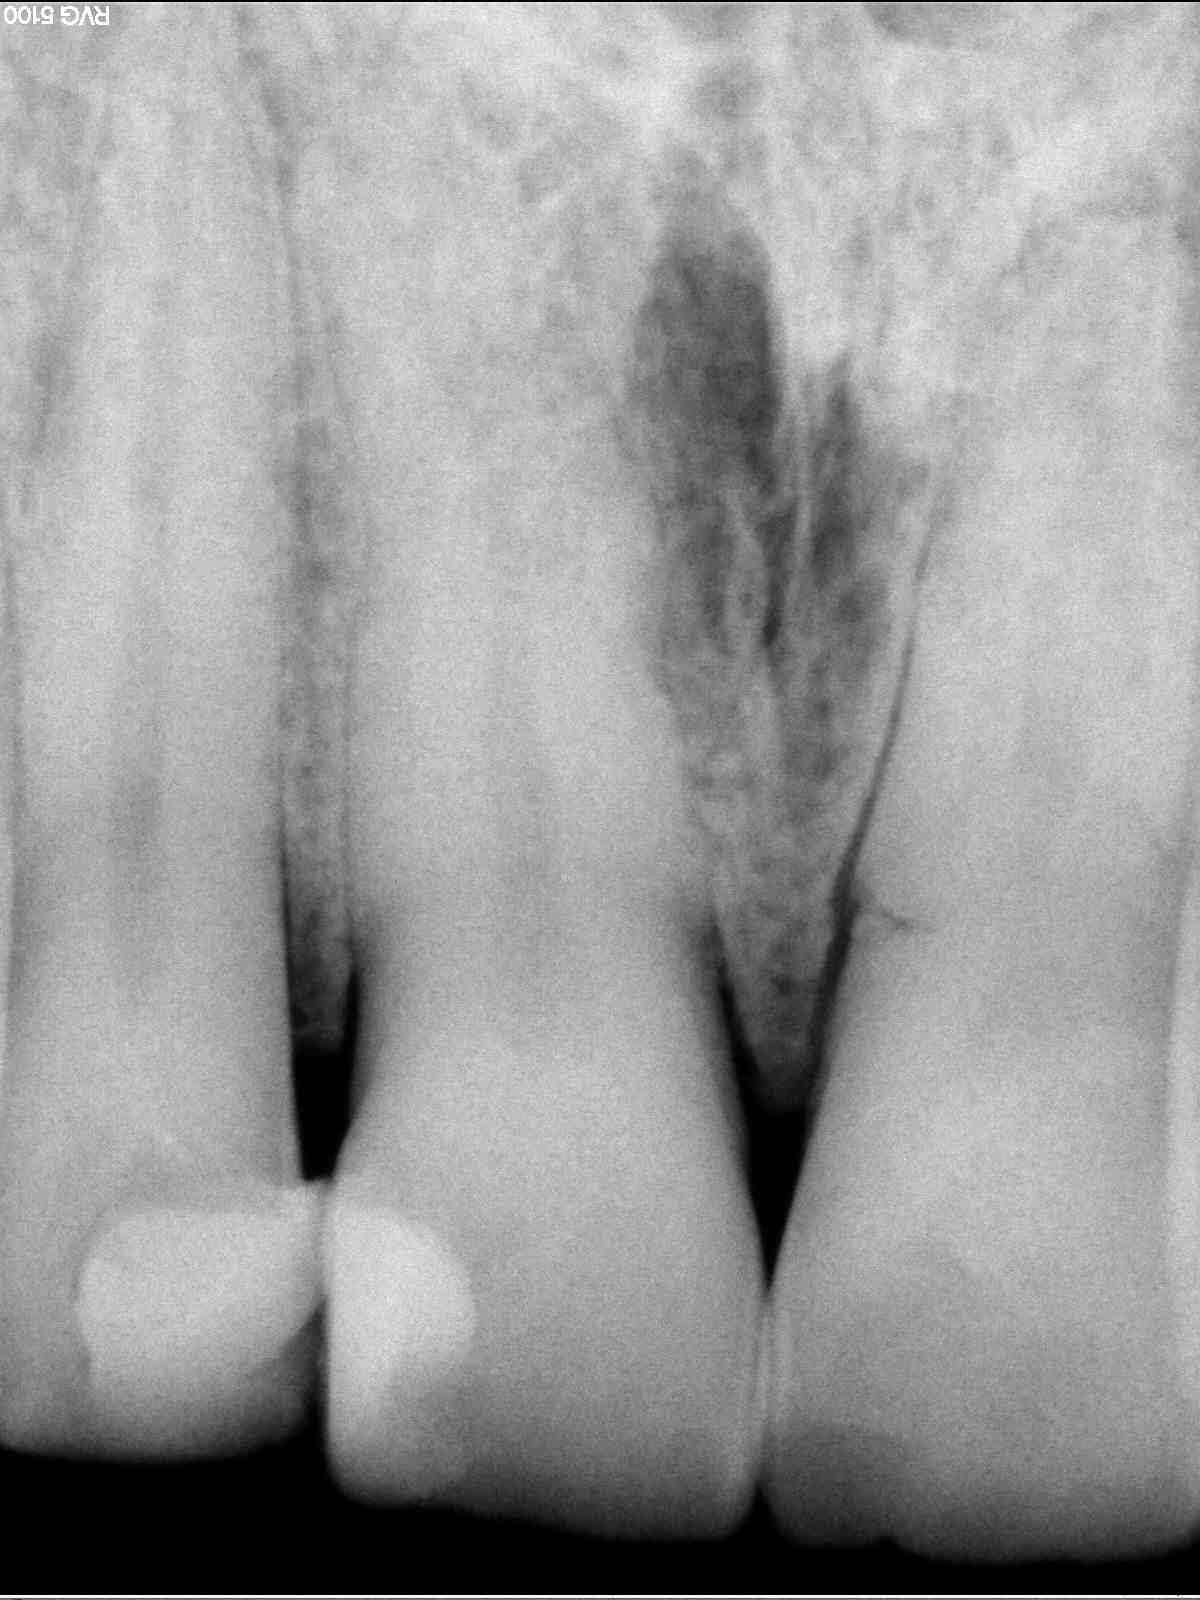

Radios1 dxb8my - Eugenol

Radios2 kprrcu - Eugenol

Radios3 auio0x - Eugenol

Radios4 pfsefa - Eugenol

Radios5 uwurgt - Eugenol

Radios6 ycayfo - Eugenol

Des inlay core... Des endos moisies... C est un français.

maladie dentaire diffuse + antécédent de choc (11 racine fracturée)